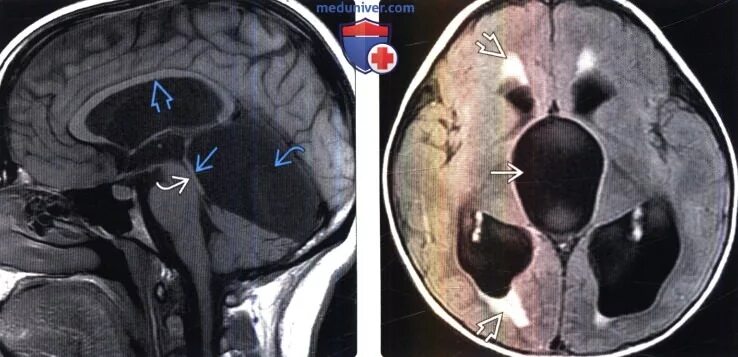

Цистерны на кт